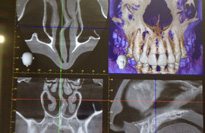

歯科用CT

インプラント治療のための術前診査や、深い親知らずや顎の病気などの精査のためにCT撮影を行なう場合があります。

CTによる撮影画像です。一般のレントゲンで見えなかった部分が容易に確認できるようになり、さらに正確な判断を行うことができるようになりました。